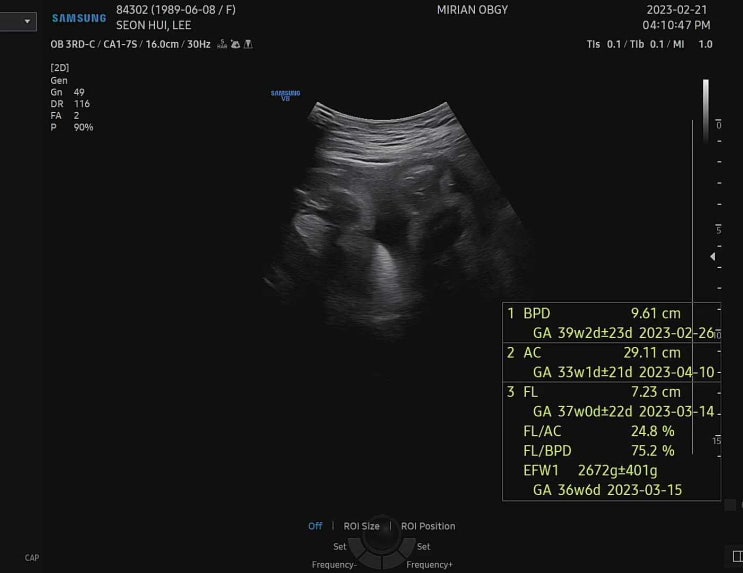

36주 1일 정기검진

이 날은 막달검사 결과 듣고! 다 괜찮은데 다음주 소변검사만 다시 하기로 하고! 초음파로는 아무리봐도 마...